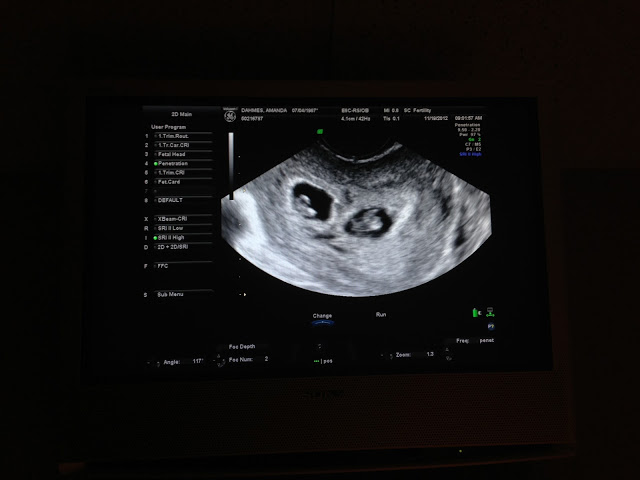

Our appointment went really well. We where there for 2 hours ( way behind) but our OB was fantastic. Took her time explained herself and what our "plan" was up to about 16 weeks. Then its all in the air and up to the babies.

I go back next week for an ultrasound and the week after for more blood tests. Then I see her 2 weeks after that.